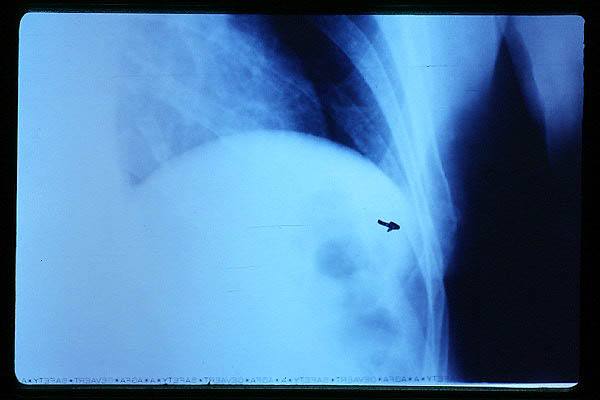

Artrosis avanzada de cadera. Anquilosis.

Artrosis anquilosante de cadera.